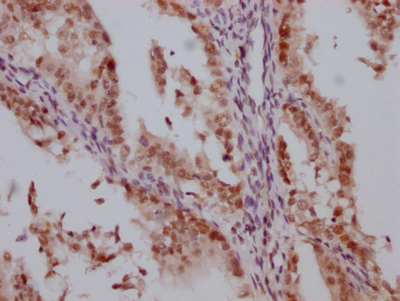

IHC image of CSB-RA906662A0HU diluted at 1:100 and staining in paraffin-embedded human endometrial cancer performed on a Leica BondTM system. After dewaxing and hydration, antigen retrieval was mediated by high pressure in a citrate buffer (pH 6.0). Section was blocked with 10% normal goat serum 30min at RT. Then primary antibody (1% BSA) was incubated at 4℃ overnight. The primary is detected by a Goat anti-rabbit IgG polymer labeled by HRP and visualized using 0.05% DAB.